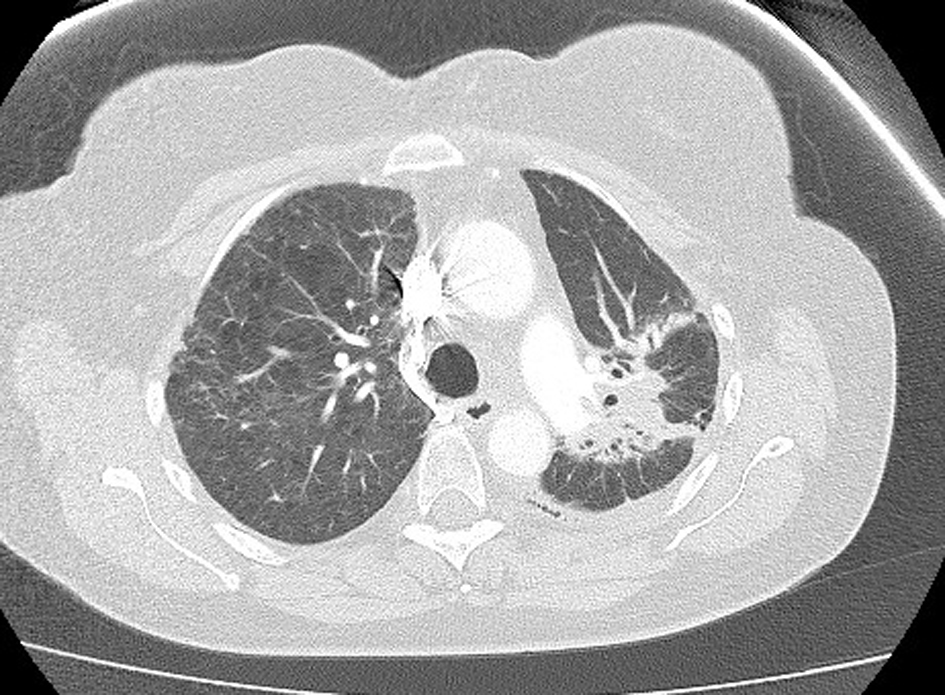

A 61-year-old female was diagnosed with stage IV (T2a, N2, M1b) NSCLC in June 2012. Positron emission tomography (PET) scan showed evidence of oligometastatic disease involving the right adrenal gland. She subsequently had a laparoscopic resection of the right adrenal gland in June 2012; pathology results were consistent with a metastatic, poorly differentiated adenocarcinoma of lung origin. She began concurrent chemoradiotherapy in July 2012, with cisplatin and etoposide, and radiotherapy (60 Gy). Treatment was complete by August 2102. Restaging computed tomography (CT) scan showed regression of the primary tumor. There was no evidence of any interstitial lung disease (Fig. 1). In October 2012, 56 days following completion of radiotherapy, maintenance pemetrexed was commenced, 500 mg/m2 every 21 days, with supplemental vitamin B12 and folic acid.

![]() Click for large image | Figure 1. High-resolution lung computed tomography before pemetrexed administration. |